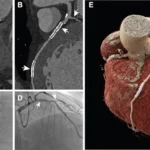

Clinical Implementation of PCCT In the last 5 years, more than 200 scientific articles have been written on photon-counting CT…